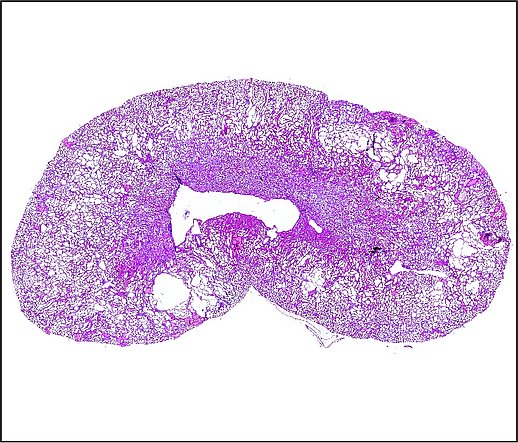

In our group we are mainly interested in the mechanisms of cyst growth in polycystic kidneys. There is a variety of polycystic kidney diseases that are often hereditary. The most frequent form is the autosomal dominant polycystic kidney disease ADPKD. It affects one in one thousand people and leads to the development of various fluid-filled cavities (cysts) in both kidneys. Cysts then grow continuously over time which causes compression of adjacent unaffected tissue which often results in loss of renal function. Cyst expansion can mainly be attributed to secretion of chloride and fluid by the cyst epithelium into the interior of the cyst. We investigate proteins but also environmental factors that may play a role in cyst secretion. Our long-term objective is to find strategies in order to inhibit cyst growth and therefore preserve renal function.

Continuous cyst growth results in progressive hypoxia in polycystic kidneys which in particular leads to expression of the hypoxia-inducible factor HIF-1α in cyst-lining cells. We analyse the effects of HIF-1α on cyst expansion.

Chloride secretion into the cyst lumen is mediated by apically expressed chloride channels. Next to the cAMP-dependent CFTR chloride channel also Ca2+-activated chloride channels are involved. Therefore, we investigate the impact of anoctamins, a new family of Ca2+-activated chloride channels, on cyst secretion.

Activation of Ca2+-activated chloride channels often follows stimulation of purinergic receptors (P2Y- and P2X receptors) by extracellular ATP. We study the relevance of purinergic receptors for secretion-dependent cyst growth.